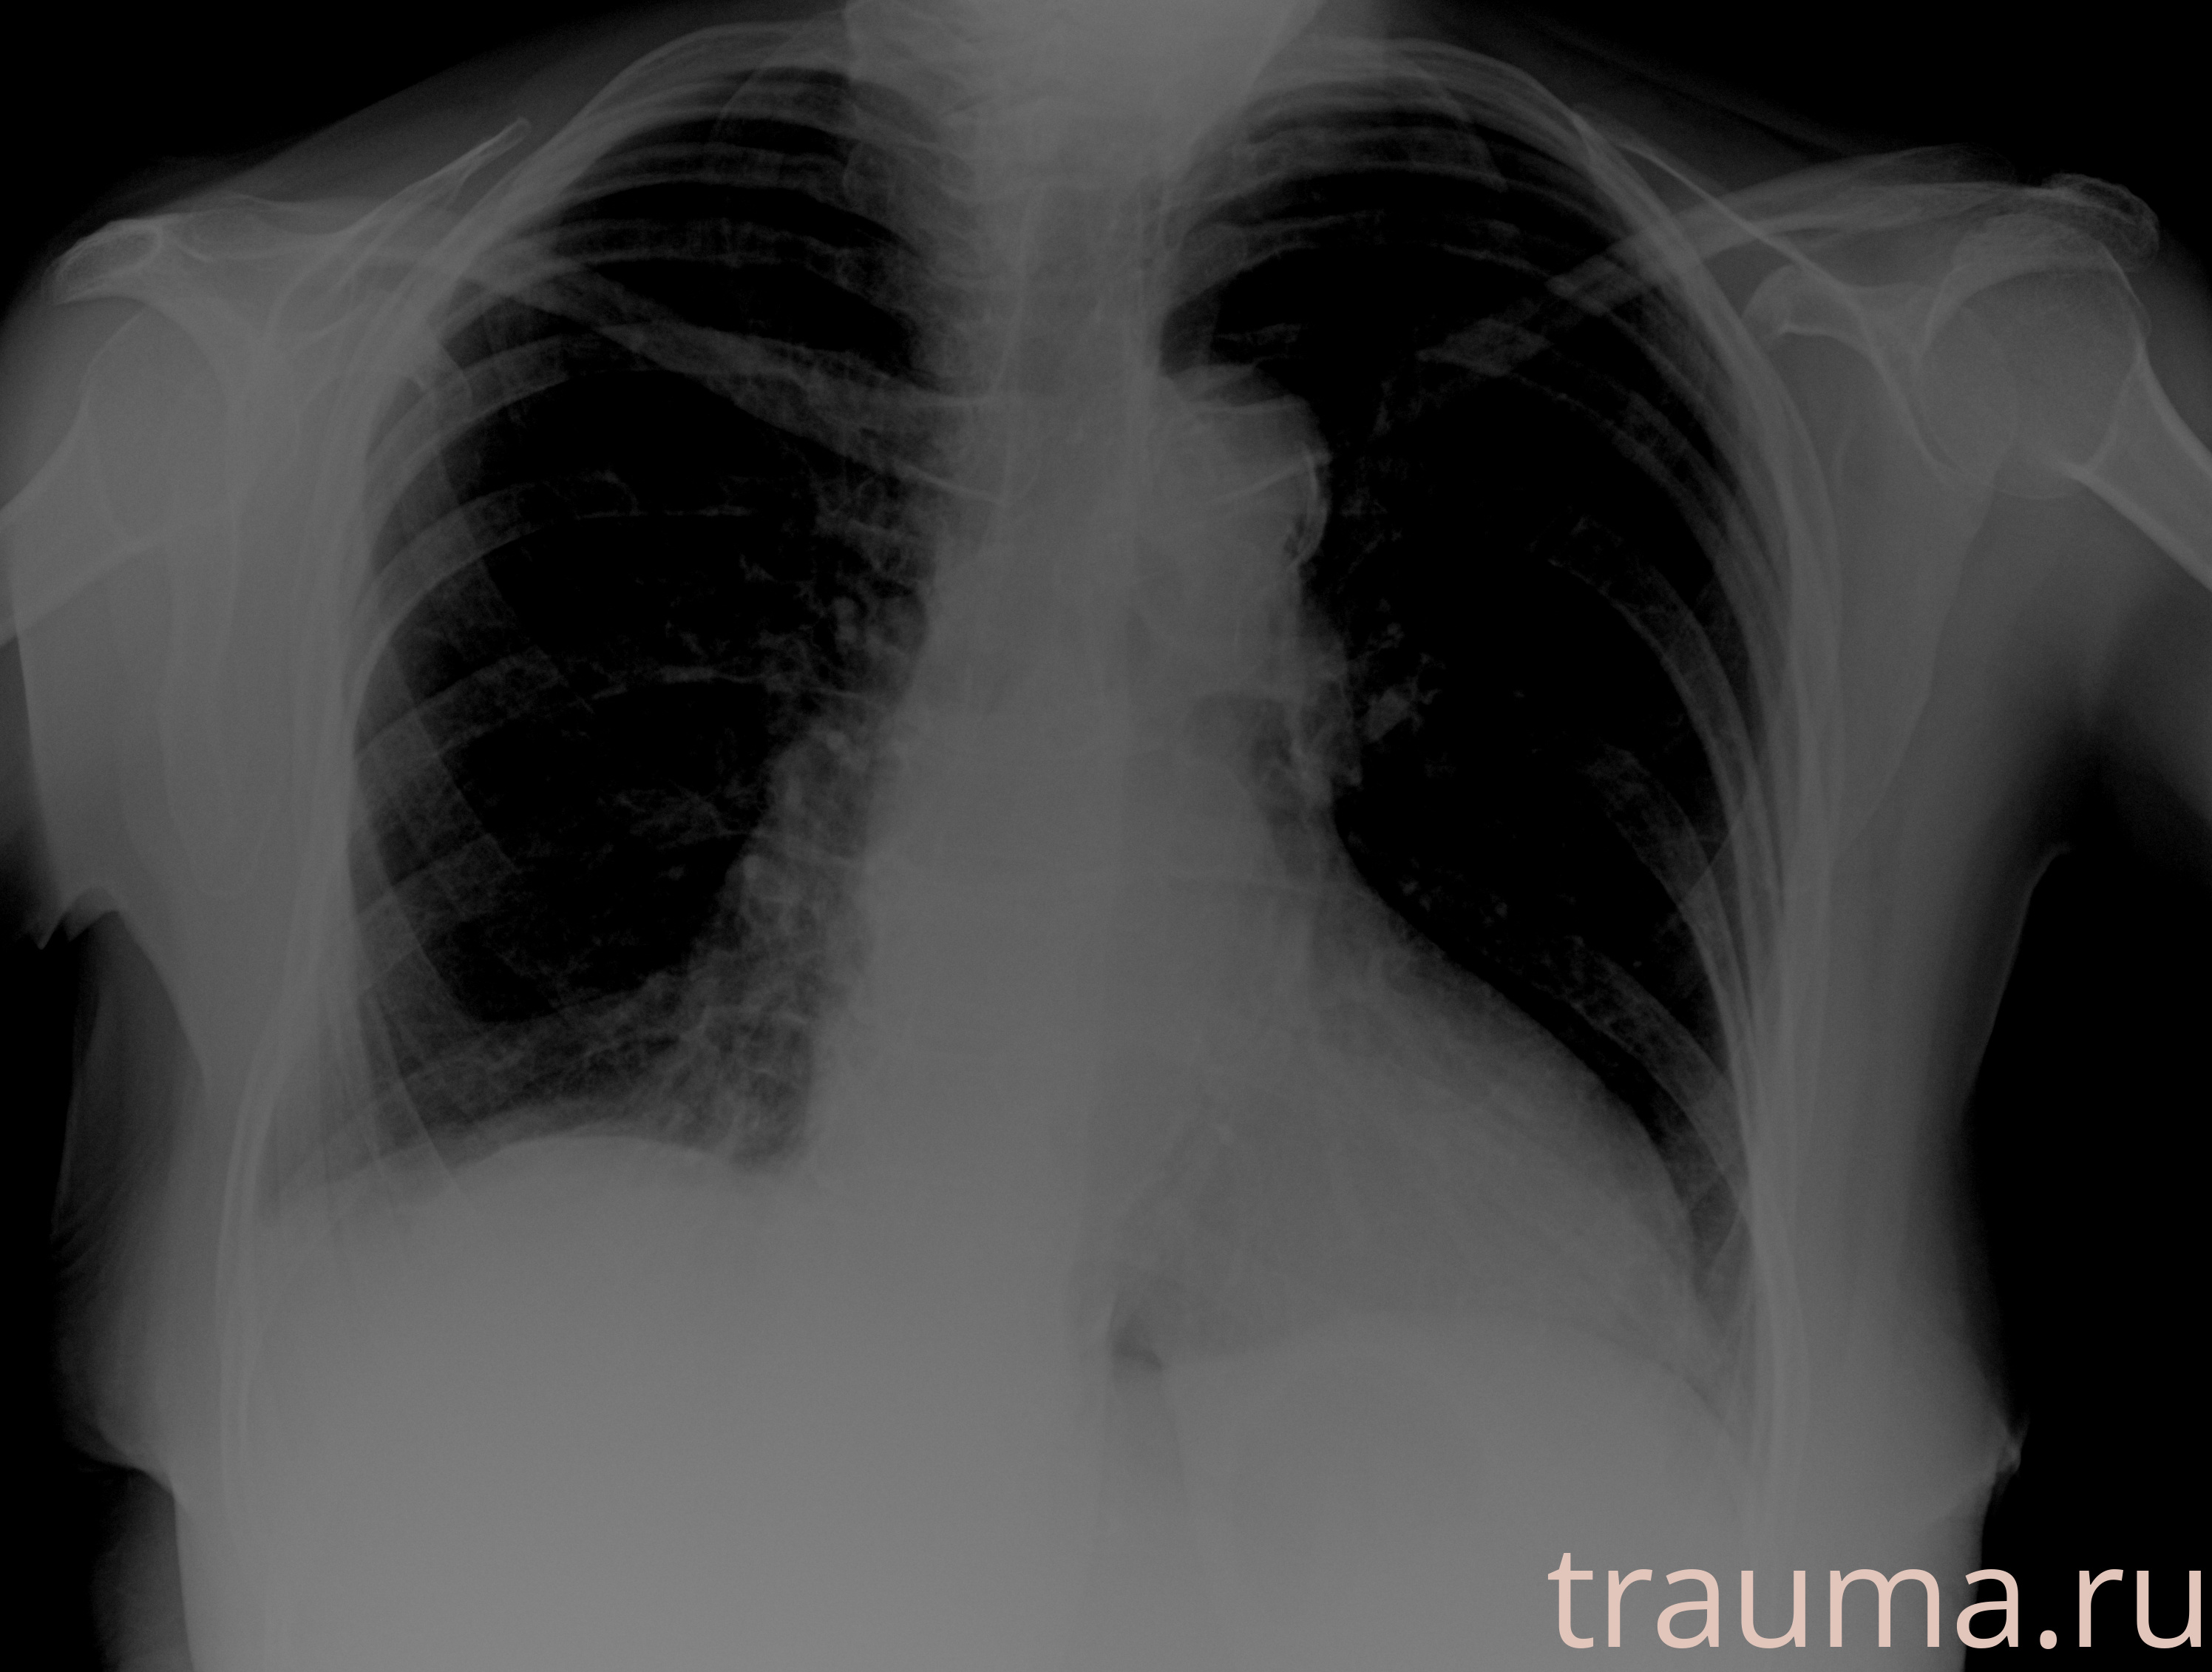

Рентген на дому: по вашему адресу приезжает врач-рентгенолог, травматолог-ортопед с мобильным рентгеновским аппаратом, проводит диагностику травмы или заболевания, делает необходимые рентгенограммы, дает рекомендации по дальнейшему лечению. Получить качественные снимки в домашних условиях возможно благодаря уникальной методике, разработанной МосРентген Центром для института  Склифосовского

при переломе шейки бедра и пневмонии от компании МосРентген Центр - партнера Института имени Склифосовского